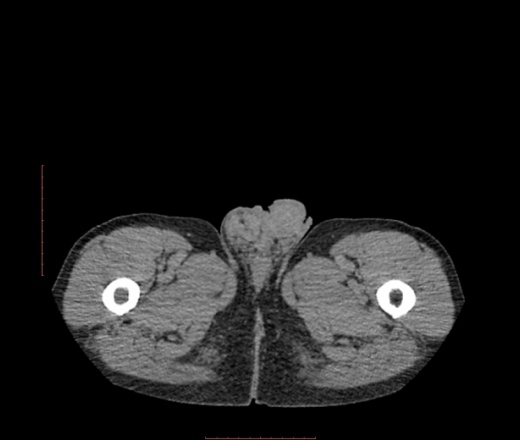

В печени похоже на гемангиому, в малом тазу вижу изменения в паховом канале, в правом яичке.

Спасибо за совет. Добавил изображнеия. В почках кисты*. А какова связь образоваия с правой паховой областью?

Липосаркома, а вниз распространяется по околопочечным пространствам.

липосаркома разной степени дифференцииации